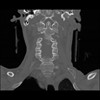

13 P.BLANDAS,,Coronal,2.000,P.BLANDAS,Coronal,